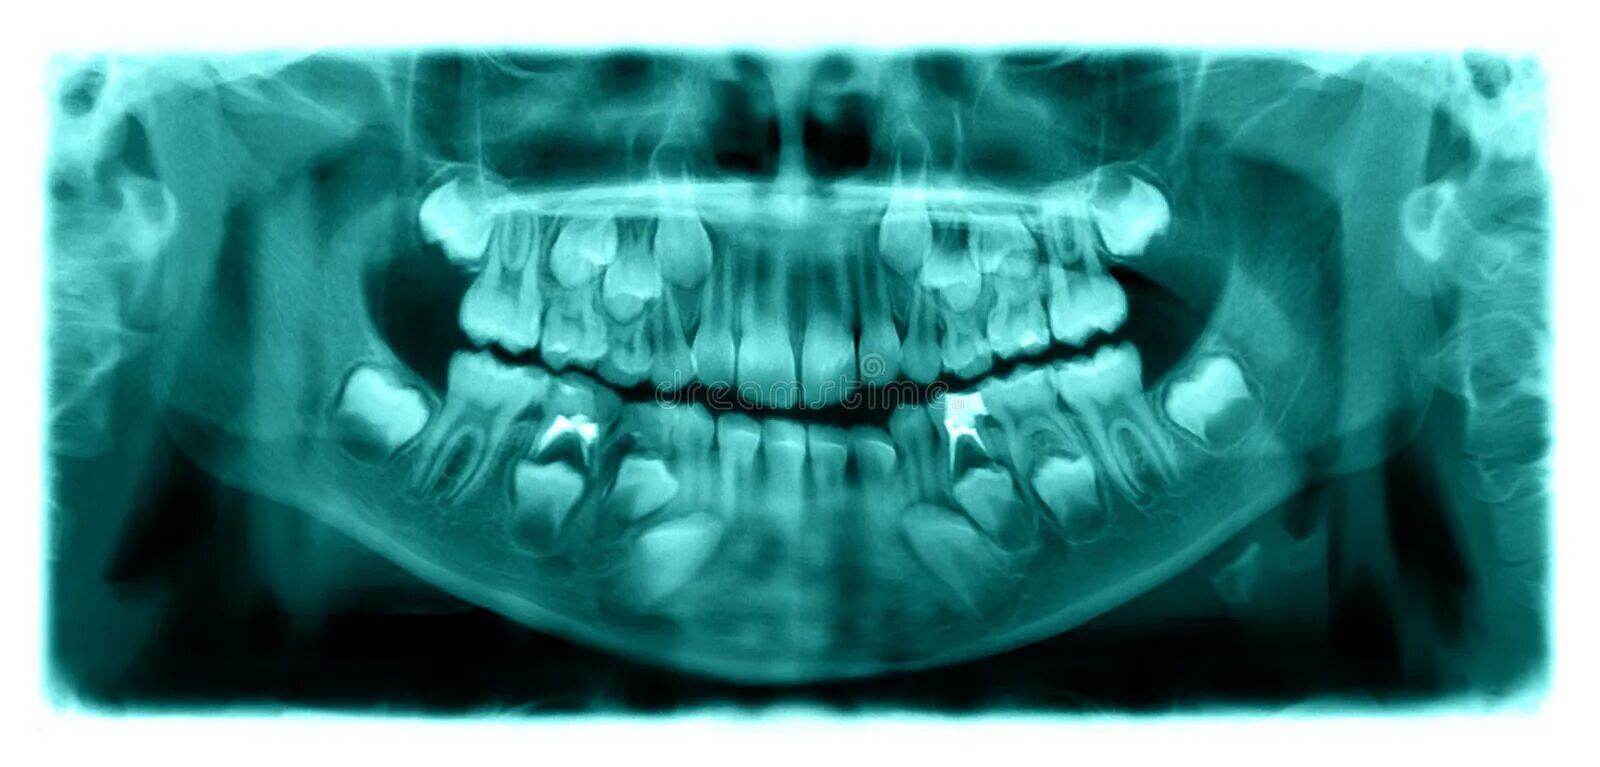

Снимок верхней и нижней челюсти